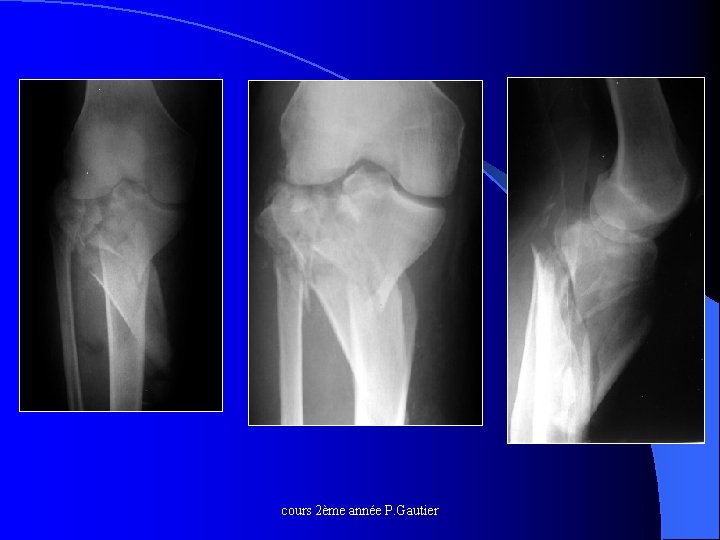

Fractures spino-tubérositaires cours 2ème année P. Gautier